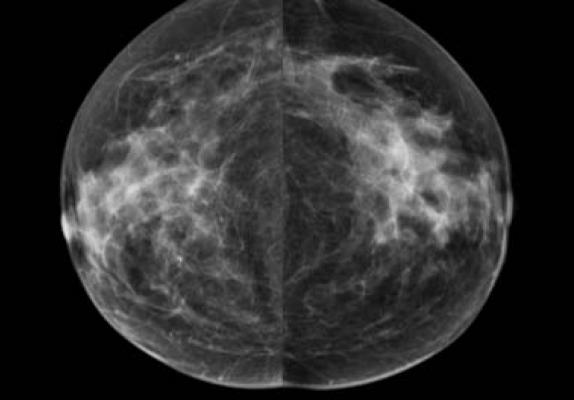

Breast density can mask cancers on mammography and is an independent risk factor for the disease. The masking effect and cancer risk are significant enough that many states have laws mandating women be notified if they have mammographically dense breasts. Despite its importance, breast density assessment is an imperfect science, and research has shown much discrepancy among radiologists in making density determinations.

Lehman and colleagues collaborated with AI expert Regina Barzilay, Ph.D., professor of computer science and electrical engineering at the Massachusetts Institute of Technology in Cambridge, Mass., and her team to develop an algorithm that can automatically measure breast density. They used tens of thousands of high-quality digital mammograms from MGH to train and test the algorithm before implementing it in routine clinical practice. Eight radiologists then reviewed 10,763 mammograms that the model had determined were either dense or non-dense tissue.

The interpreting radiologist accepted the algorithm’s assessment in 10,149 of the mammograms, or 94 percent. Lehman noted that the 94 percent agreement rate between the radiologists and the algorithm does not necessarily mean the machine was wrong in 6 percent of the cases. Reader variability could affect the disagreement because radiologists visually assess breast density, which is subjective and qualitative.